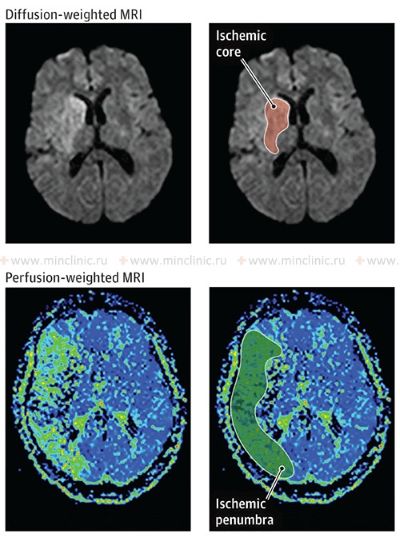

Treatment for stroke caused by cerebral embolism encompasses managing the acute phase to minimize brain damage and implementing strategies for secondary prevention to reduce the risk of future embolic events [1, 16]. In the acute setting (first hours to days), a primary focus is often on maintaining adequate cerebral perfusion pressure to support blood flow to the ischemic penumbra (the area surrounding the core infarct that is at risk but potentially salvageable) [16]. Current guidelines generally recommend permissive hypertension (allowing blood pressure to remain somewhat elevated) unless it exceeds very high thresholds (e.g., >220/120 mmHg, or >185/110 mmHg if thrombolysis is given) or there are specific contraindications [16]. Aggressively lowering blood pressure should generally be avoided unless necessary for specific conditions (e.g., aortic dissection, acute heart failure) [16]. Conversely, significant hypotension (low blood pressure) should be treated promptly but cautiously, as excessive blood pressure elevation might worsen cerebral edema or increase the risk of hemorrhagic transformation [1, 16]. Cerebral edema (swelling) typically develops over 2-3 days following a significant infarction and may peak around day 3-5, potentially persisting for up to 10 days or longer in severe cases [1].

While reperfusion therapies (like intravenous thrombolysis or mechanical thrombectomy) aim to restore blood flow by dissolving or removing the embolus [16, 19], there's a theoretical concern that reperfusion into damaged tissue might increase edema or hemorrhagic transformation [1, 8]. However, the benefits of timely reperfusion in salvaging the penumbra generally outweigh these risks in eligible patients [16, 19]. Symptomatic cerebral edema in embolic infarction tends to follow two main patterns with significant clinical implications [1]: